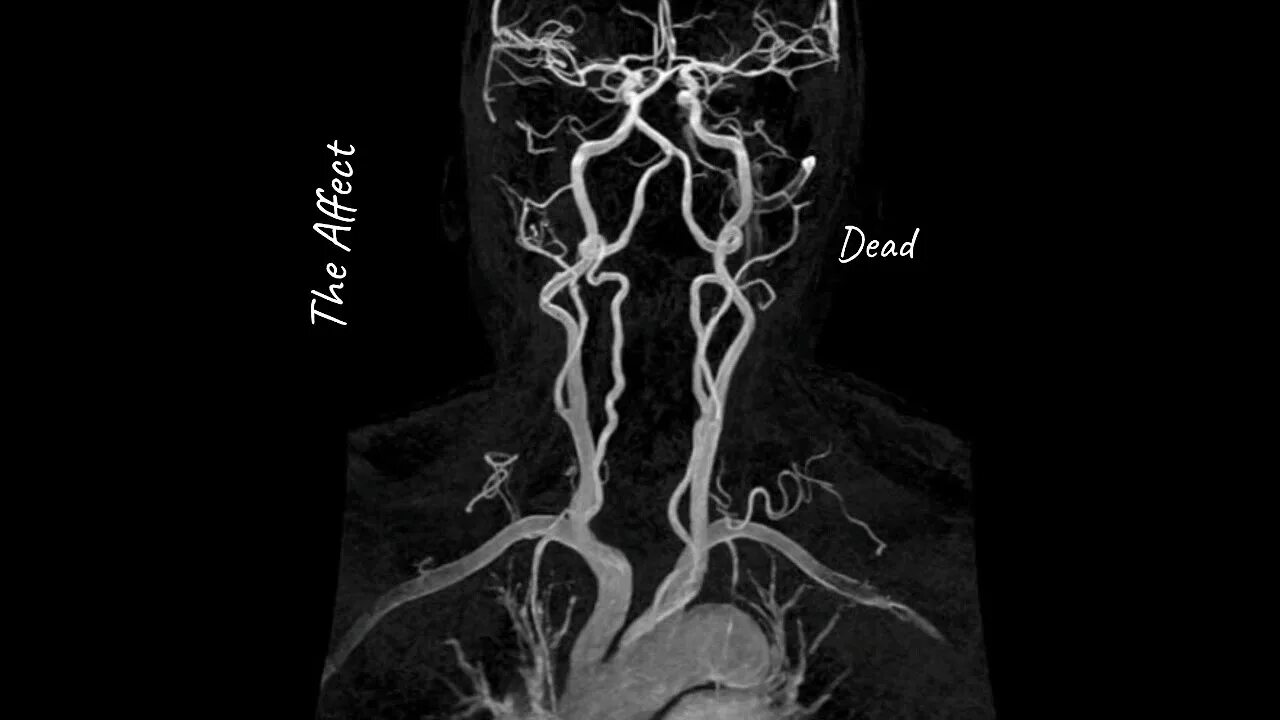

Что покажет мрт головного мозга с контрастом